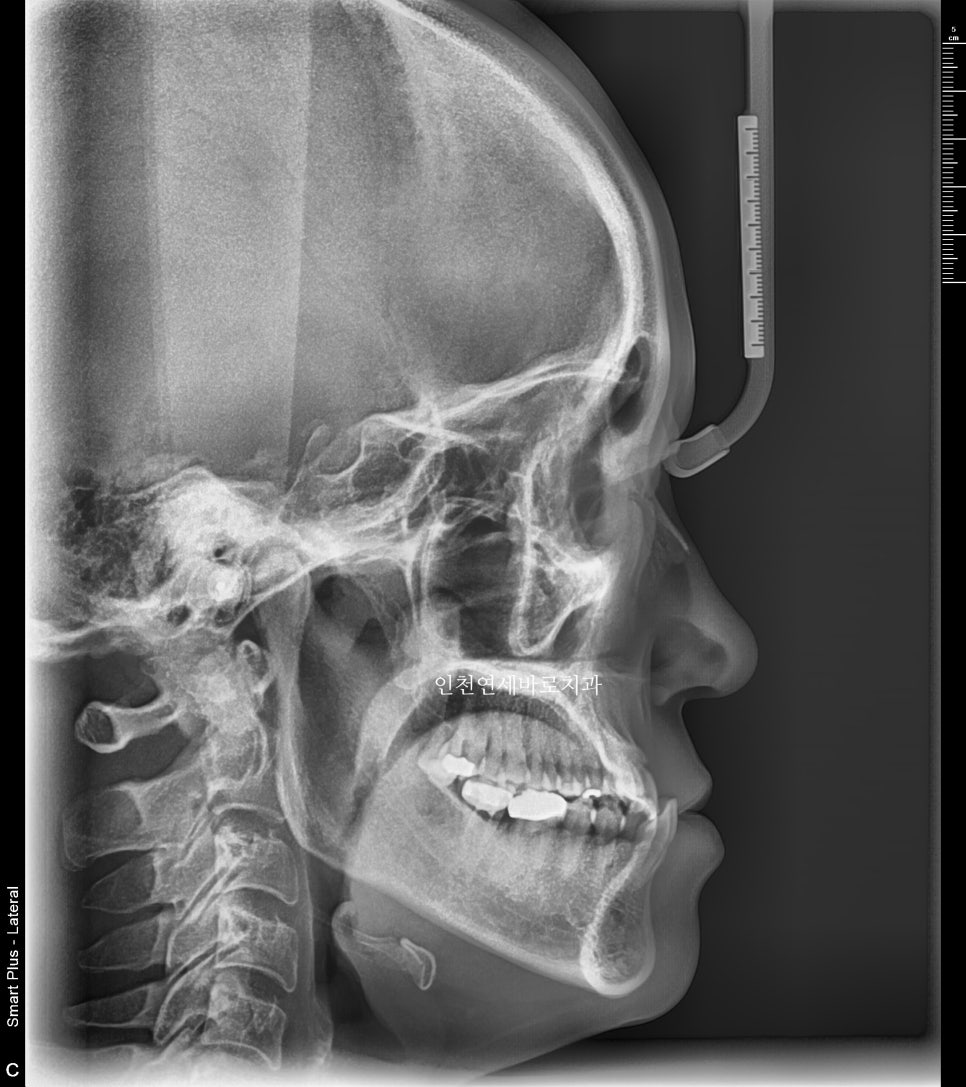

전후 엑스레이입니다

양악수술은 아니기에 큰 변화는 아니지만 안모의 개선을 확인 가능할겁니다.